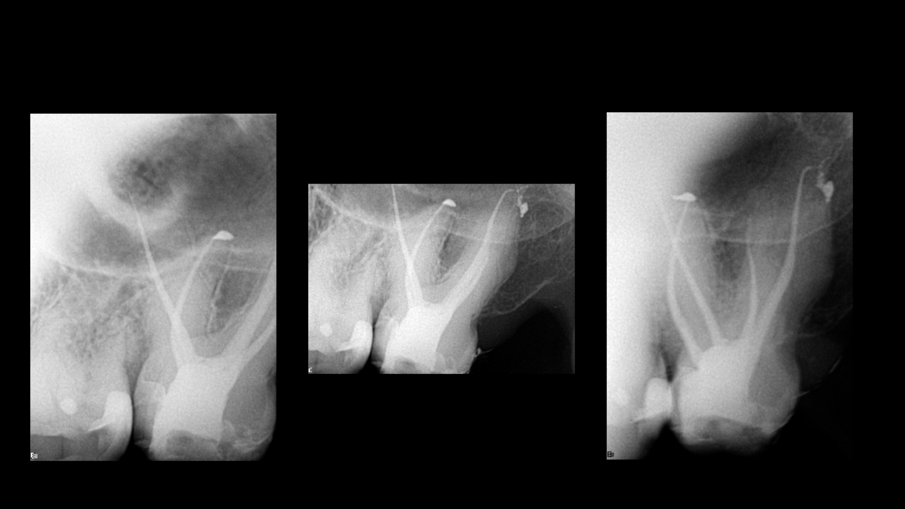

Pomoću ovog softvera može se vizualizovati 3D model zuba sa kanalima ucrtanim sa njihovim približnim radnim dužinama, dajući nam predstavu šta da očekujemo (Sl. 4). Na primer, u ovom slučaju, prosečna radna dužina je bila oko 27 mm za ovaj drugi maksilarni molar sa četiri kanala i ovakvom anatomijom — ja ove slučajeve zovem dupli espreso jer su mali izazov. Na primer, distalni kanal je imao oštru krivinu poput kuke na vrhu. Svi ovi podaci mogu pomoći u odabiru sekvence endodontskih turpija za oblikovanje i čišćenje sistema kanala korena. Traverse i ZenFlex turpije (Kerr Dental; Sl. 5) su korišćene za oblikovanje kanala. U distalnom korenu, turpija 30/.04 nije korišćena u poslednja 2 mm, kako bi se izbeglo bilo kakvo deformisanje ove oblasti. Irigacija je obavljena prema Sleimanovoj sekvenci irigacije (objavljeno u roots magazinu 1/2014). 3D obturacija kanala izvedena je sa Elements IC obturacionim sistemom (Kerr Dental; Sl. 6).

Sl. 4: 3D rekonstrukcija kanala u različitim bojama, koja prikazuje detaljnu dužinu segment po segment za svaki kanal